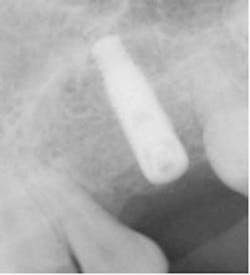

By Alfred L. “Duke” Heller, DDS, MS, and Robert L. Heller, DDSObviously most general practitioners would agree that financially they would like to increase their office income by doing simple implant placement and restoration, thus keeping the fees for those services in their own cash flow. They also realize that implant dental treatment is a prosthetic discipline with a surgical component! Simple implant surgery starts with mounted models and pre-surgical diagnosis and treatment planning. The result of proper planning will produce a surgical template to help the doctor place the implant where it can be restored. Many times the implant placement comes back from a referring office with the implant out of alignment, and then it becomes compromised at the point of trying to make the prosthetics adapt to a misaligned implant.Considering that the average implant fee is $1,500 to $2,000 per implant and the abutment and fixed crown fee is approximately another $1,500, that is roughly $3,000 to $3,500 that could stay in the general practitioner’s own cash flow to help in this trying economic time. General practitioners can become as skilled as specialists in placing dental implants and should consider placing simple implants for their patients. Patients prefer to have their own dentist treat their dental implant needs rather than go to a different office for treatment.So why do so few general dentists place implants?It can be speculated that many don’t do implants because they don’t like surgery. Some dentists say they don’t feel adequately trained to watch a slide presentation at an implant course and then place implants in their patients. Some say they would like to place their first few implants with someone looking over their shoulder. Others feel that if they need to graft bone at the time of implant placement or before implant placement, they don’t know what materials to use. Bone grafting materials are becoming increasingly abundant in the marketplace. Doctors should seek training where the presenters are not paid to speak about certain bone grafting materials or a certain implant system. They should also seek to find a mentor or individual they can call on the telephone with surgical or prosthetic questions.Case reportA 22-year-old female presents with tooth No. 11 missing. History of patient is that the tooth was lost four years ago due to trauma. Patient would like for the general dentist to place the implant so she can get rid of her present flipper. The initial photo shows that the ridge appears to be sufficiently wide to accept an implant in the maxillary left cuspid area (Fig. 1). Upon tissue reflection, the underlying bone presents with a labial and lingual defect (Fig. 2). Options include a block bone graft or particulate graft with a barrier. A decision was made to use irradiated bone (80%), tricalcium phosphate (20%) mixture, together with Platelet Rich Plasma (PRP) mixture after decortications were done with a 700 XXL bur (Fig. 3). The barrier selected was the Inion GTR Barrier (Reimser Inc., Durham, N.C.) using small tacks (Salvin Dental, Charlotte, N.C.) to maintain the ridge (Fig. 4a). A plasticizer is used, which hardens the membrane to allow maturity of the bone graft without pressure necroses from food or removable appliance. Fig. 4b shows a side view showing the bone mixture under the Inion barrier. PRP (Clinseal centrifuge from Salvin Dental, Charlotte, N.C.) was used in the bone grafting mixture as well as in the completed sutured tissue to enhance bone and tissue growth. PRP was injected under the tissue flap to aid in bone growth at the end of procedure. Six months later, the ridge exposure measured 10 mm buccal-lingually (Fig. 5). As is evident in the photo showing buccal and lingual bone growth, which would not have been obtainable with a block graft, it would have only produced bone on the buccal thin ridge.A 3.7 mm implant was placed easily into the grafted site, leaving adequate buccal and lingual supporting bone for the implant (Fig. 6). Fig. 7 shows tissue closure with 43-0 vicryl sutures (Ethicon by Johnson and Johnson, Langehorne, Pa.). A periapical X-ray shows implant placement in grafted bone (Fig. 8).

Fig. 6 shows placement of a 3.7 mm Zimmer implant in the 10 mm wide new bony receptor site.

Fig. 8 shows an X-ray of 3.7 mm implant placement.